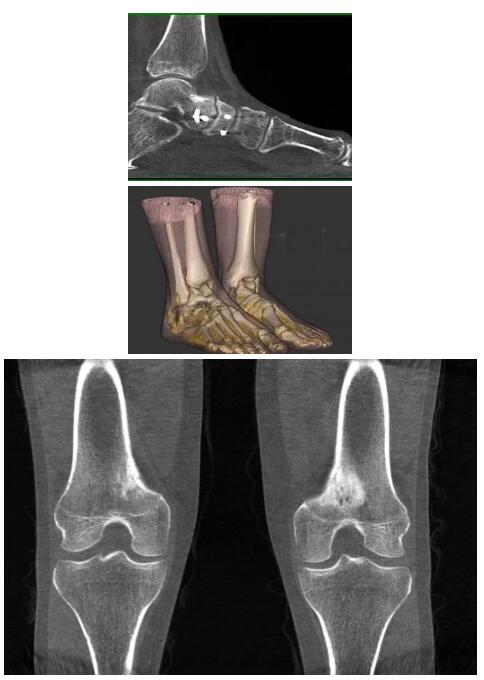

比如上面這款專用于足部和踝部掃查的CT成像系統(tǒng),患者在進(jìn)行CT掃查時(shí)只需要站在上面即可,雙腳站或者單腳站都可以,當(dāng)然,如果患者不是那么方便站著做完CT掃查,也可坐在上面。

這款CT掃查系統(tǒng)自帶屏蔽裝置,它的體積非常小,僅需要極小的空間即可,并不像常規(guī)CT那樣需要一間單獨(dú)的檢查室。此外,這種CT掃查的速度非常快,僅需30秒左右可以完成檢查,輻射劑量相對(duì)常規(guī)的CT要少許多,尤其適合醫(yī)院的骨科使用。

而患者站著做足部或者踝部做CT檢查還有個(gè)好處是,可以檢查患者在負(fù)重的情況下,骨關(guān)節(jié)的真實(shí)情況,而躺著做CT掃查時(shí)未必能看出來。負(fù)重CT掃查特別是對(duì)于受傷的運(yùn)動(dòng)員或者舞蹈員來說意義更大,能夠更準(zhǔn)確地評(píng)估傷情,幫助他們盡早復(fù)原。

以下是這些“特立獨(dú)行”的CT所拍出來的圖像: